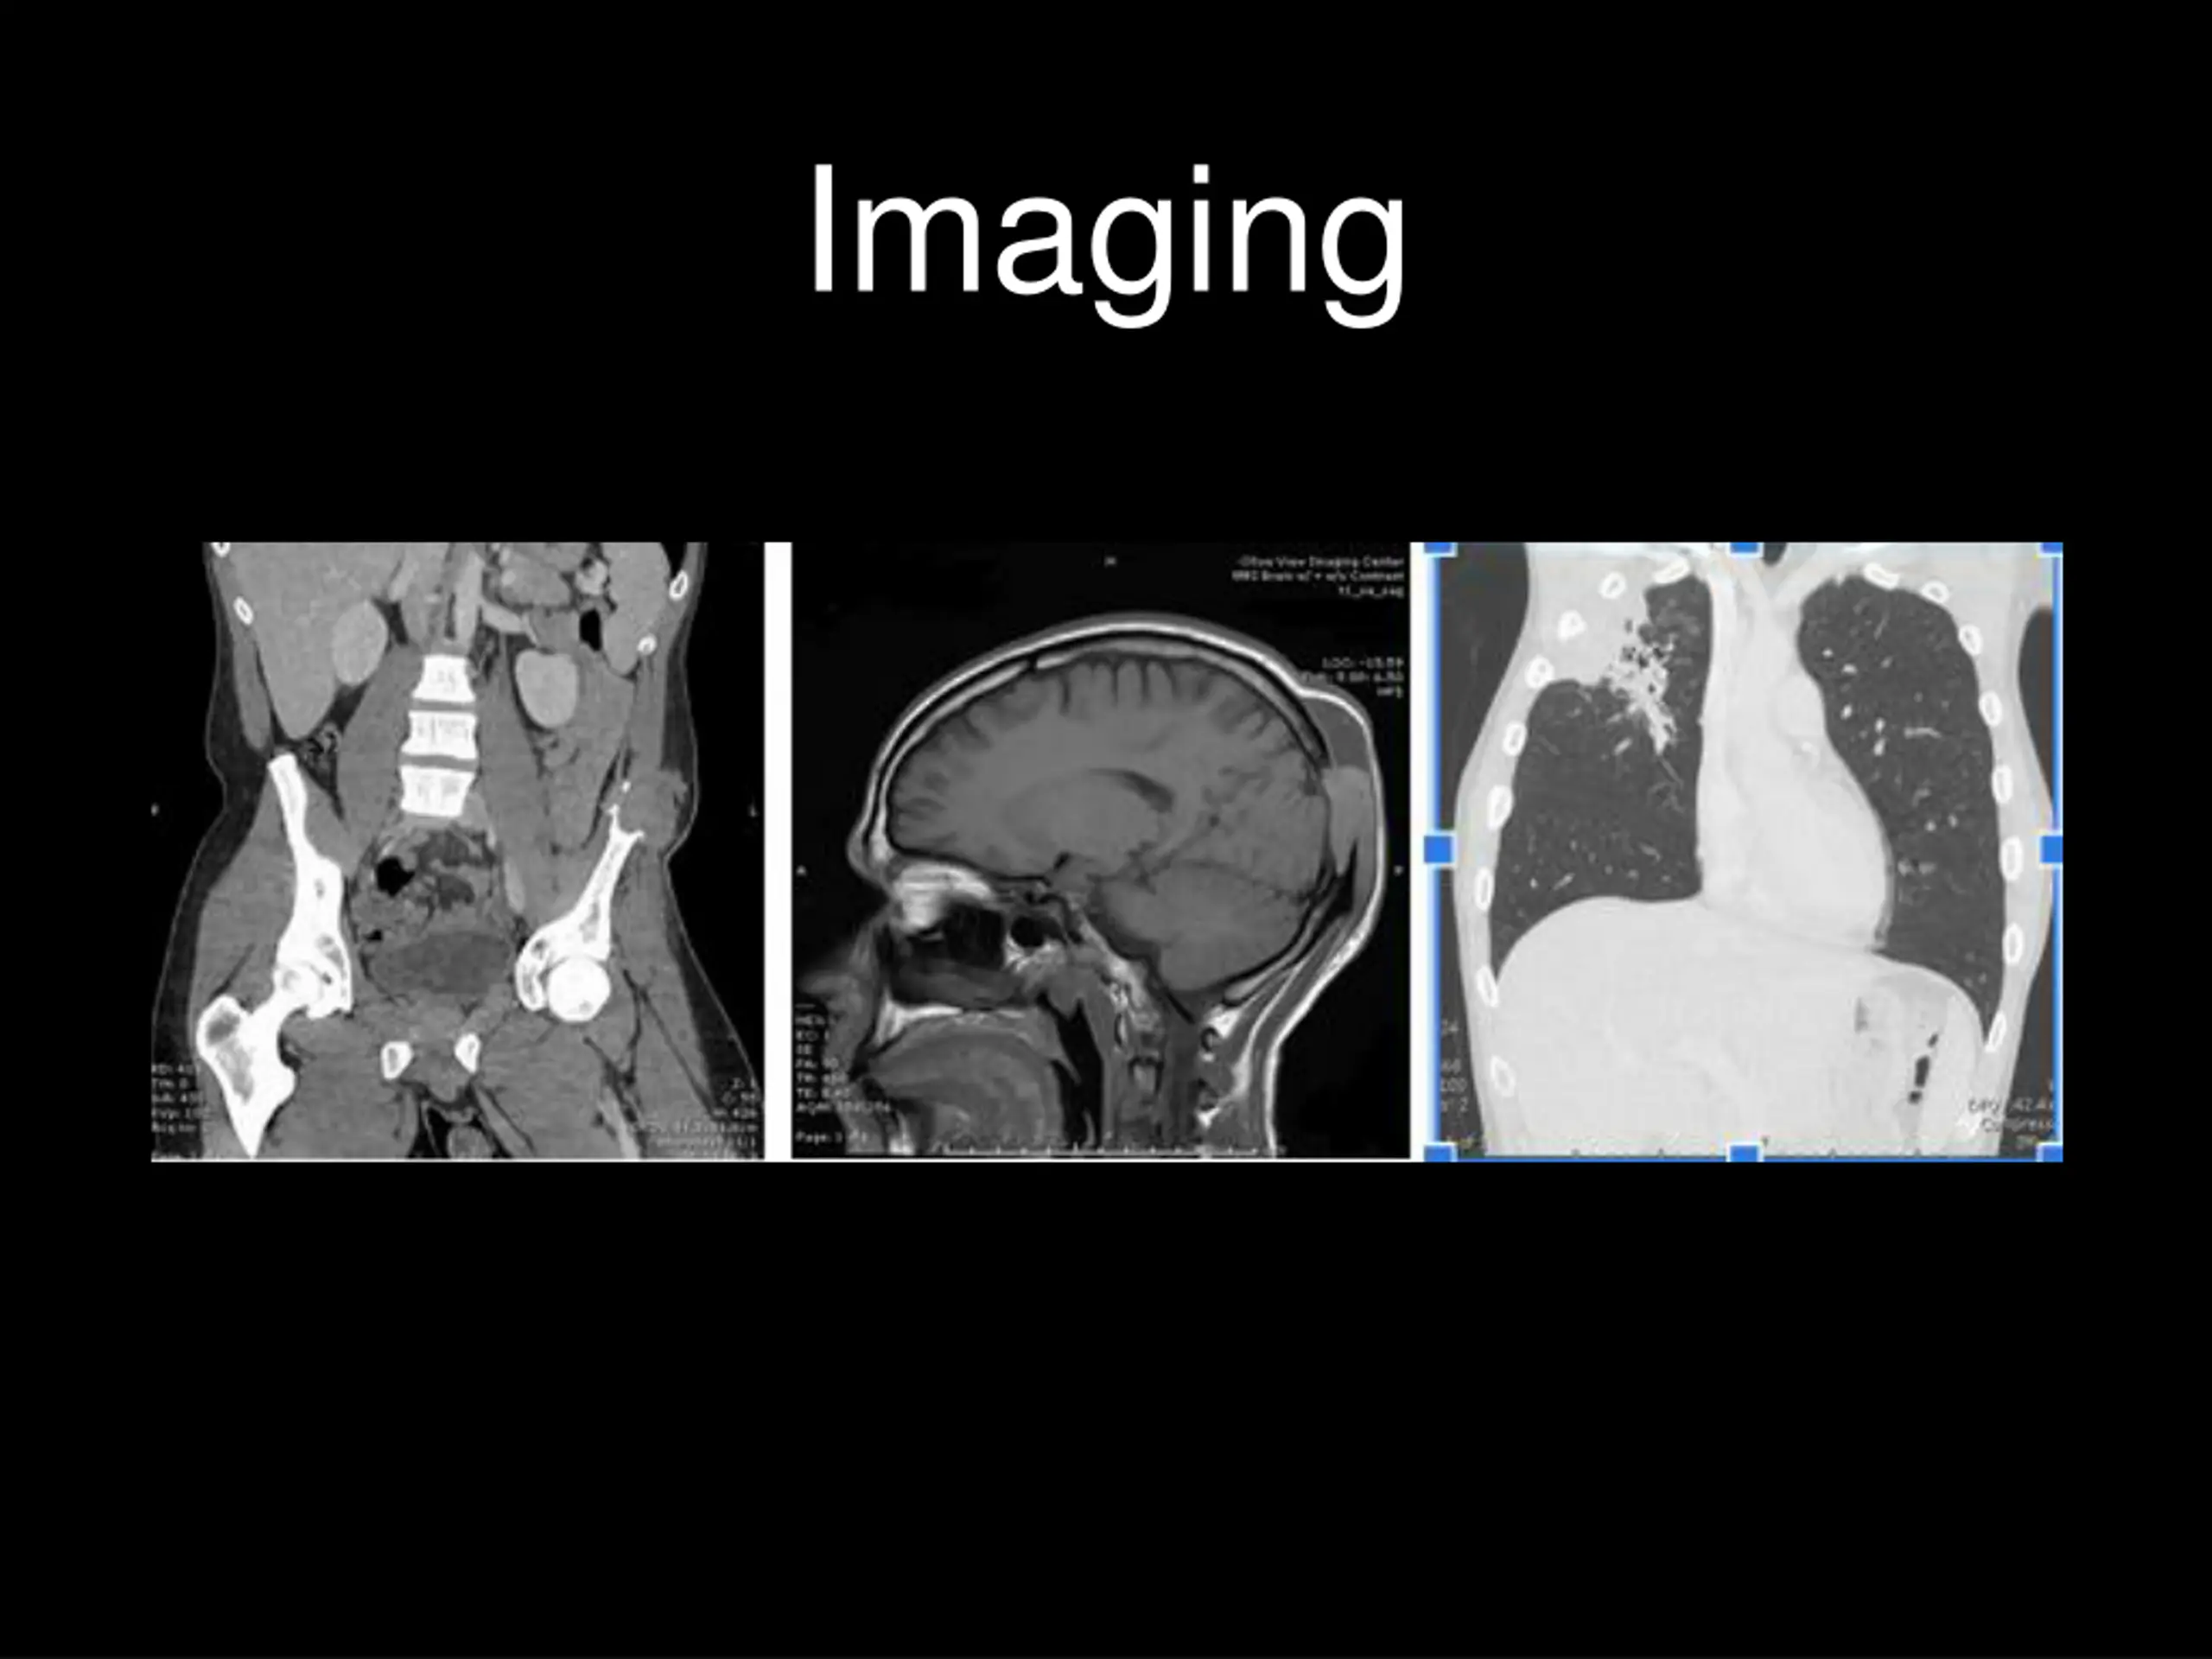

Hospital Course Given the subacute involvement of multiple organs, a disseminated atypical infectious process was suspected early with Blastomyces of concern given the patient s origin. Skin punch biopsy of the right wrist staining with GMS and PAS-D revealed spherical double-contoured fungal yeast with broad based buds in multinucleated giant cells, with dermal granulomatous inflammation and micro-abscesses consistent with blastomycosis. The patient was started on liposomal amphotericin within 72 hours of presentation given concern for CNS involvement. Fungal cultures from both the draining flank abscess and right wrist skin biopsy grew Blastomycosis dermatitidis identified via DNA probe on day 17 confirming the diagnosis of disseminated blastomycosis.